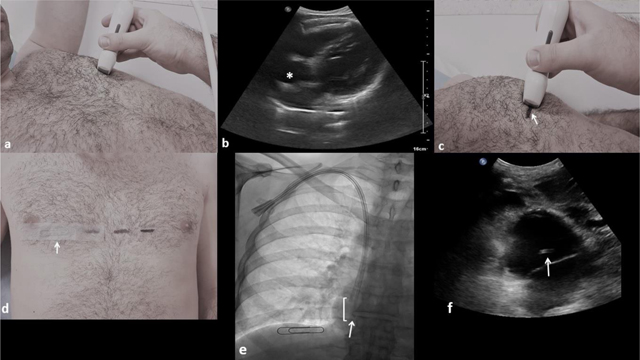

Figure 1

(a) The US probe is placed transversely in a left anterior intercostal space. (b) The right atrium is localized (asterisk) by a left intercostal approach. (c) A horizontal line is drawn on the skin (arrow) at the probe’s level (mid-width). (d) A paper clip (arrow) is stick on the skin at right (midclavicular line), at the same horizontal level that the drawn skin marker, corresponding to the atrial floor. (e) Antero-posterior fluoroscopic image of the chest showing a 23 cm inserted long term hemodialysis catheter through the right internal jugular vein with its distal tip (arrow) located above the paper clip, so the entire functional part (square bracket) is located inside the right atrium. (f) Subxiphoid US view confirming the distal catheter tip position inside the right atrium (arrow).